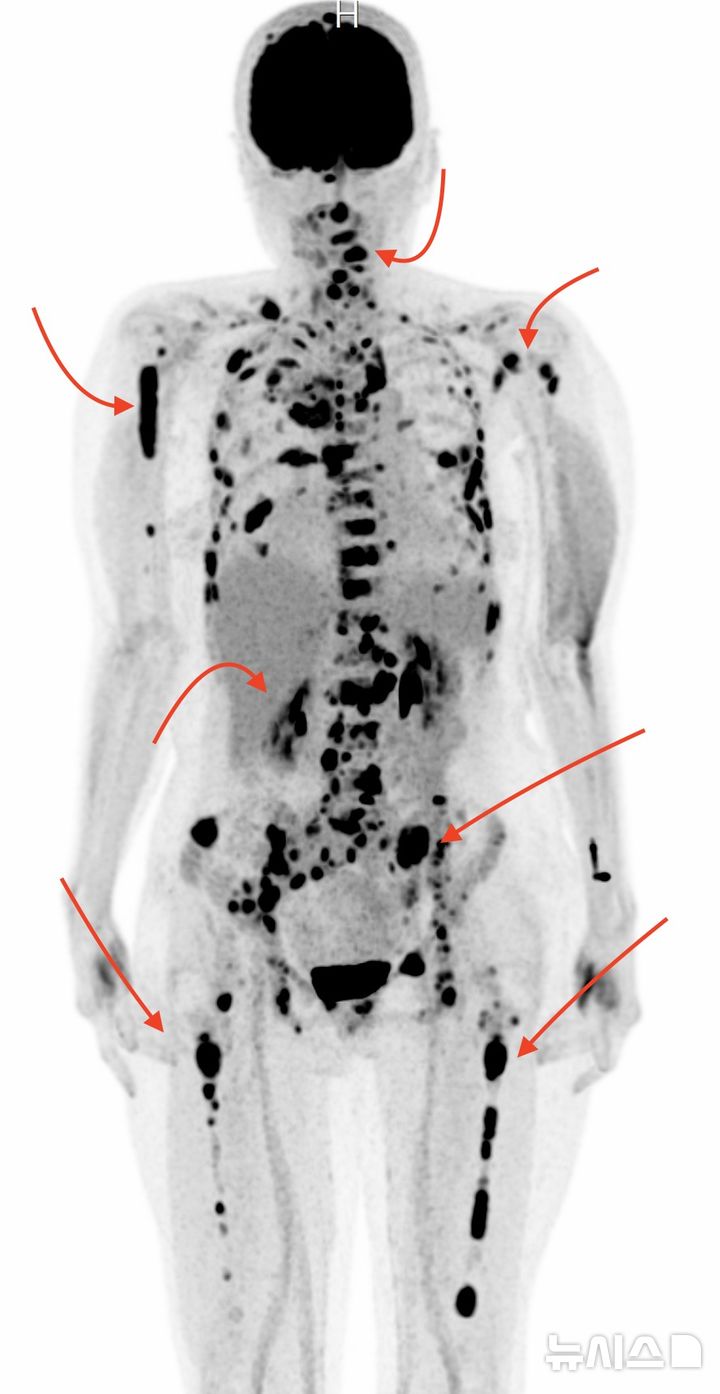

[서울=뉴시스] 전구진단 선별 없이 다발골수종으로 진단된 중증 환자의 PET CT 영상. (사진= 서울성모병원 제공)